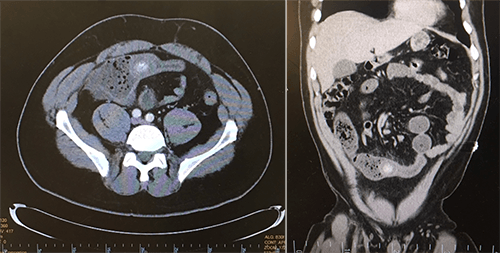

A 50-year-old male presented to the emergency department with a three-month history of episodic, generalized abdominal pain, which acutely worsened one day prior to arrival. The patient reported nausea and vomiting. On physical exam, the patient’s abdomen was distended and tender; there was no guarding or rebound. Bowel sounds were absent. A nasogastric tube was placed which produced 2L of bilious fluid. The patient had a computerized tomography (CT) scan, which showed a foreign body in the small bowel causing obstruction. It was noted that there were no gallstones present in the gallbladder, no air in the biliary tree, no pericholecystic fluid, and no common bile duct dilation. The foreign body was thought to represent a stone of natural composition in the distal small bowel. Despite lack of other defining features for gallstone ileus, the preoperative diagnosis was a gallstone ileus.

Figure 1a. Sagittal CT Scan image of fecalith causing small bowel obstruction. Figure 1b. Coronal CT Scan image of fecalith causing small bowel obstruction with view of gallbladder.

Figure 1b. Coronal CT Scan image of fecalith causing small bowel obstruction with view of gallbladder.